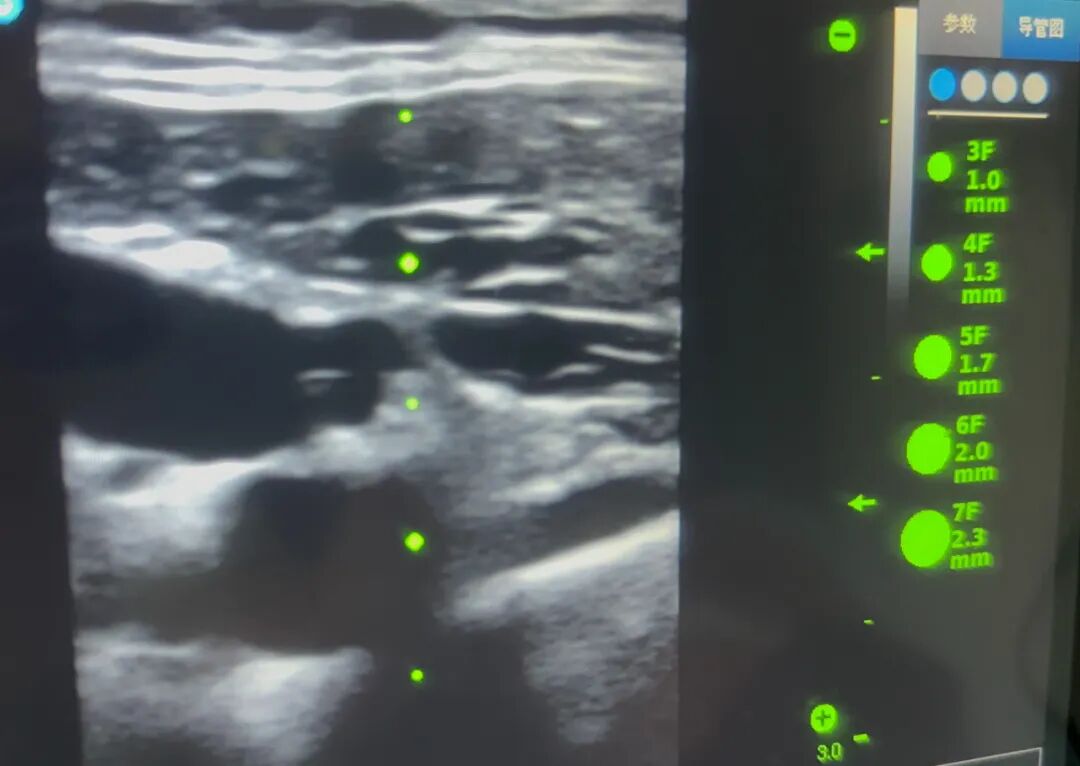

面对这一棘手情况,科室迅速启动多学科协作机制,邀请PICC专科门诊参与会诊。专科护士凭借丰富经验,结合超声定位技术,清晰掌握患者深部血管走行,成功置入一根中长导管。整个操作精准、微创,一举突破患者体型带来的穿刺困局,为后续治疗的顺利实施奠定了坚实基础。